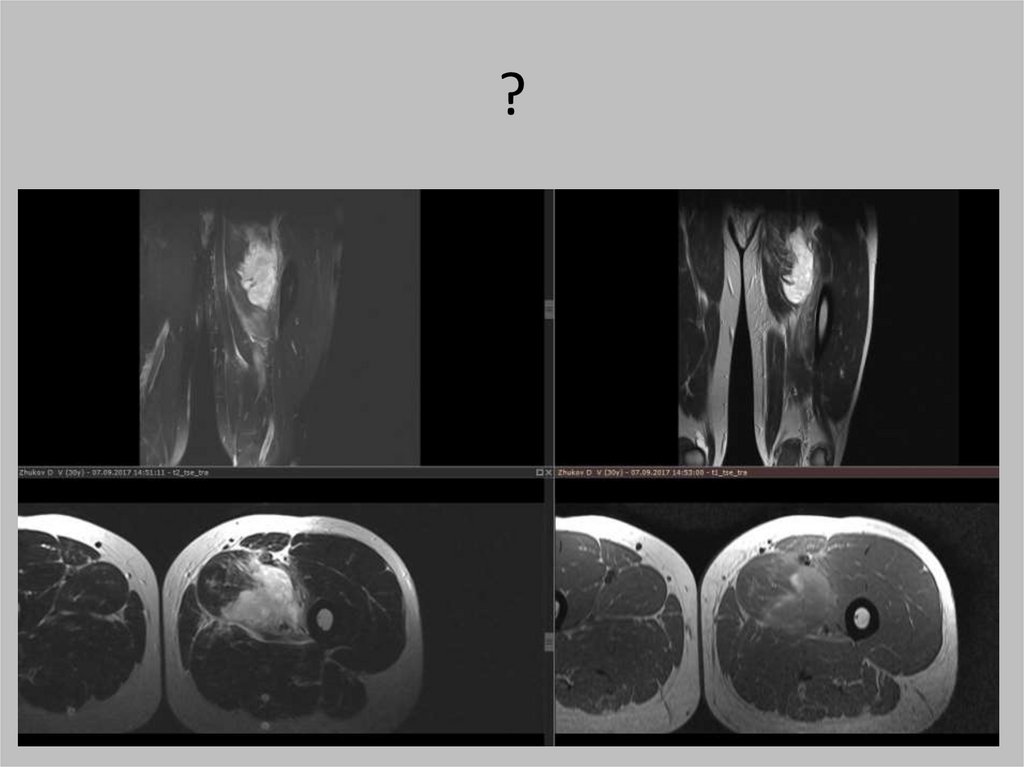

?